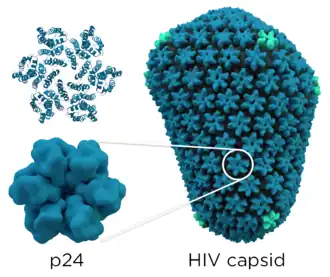

Mit der Innenseite der Membran sind die durch gag codierten Matrixproteine p17 assoziiert. Im Inneren des Virions findet sich das Viruskapsid, das aus den durch gag codierten Kapsidproteinen p24 aufgebaut ist, deren Struktur schrittweise 1996[15] und 1997[16] aufgeklärt wurde. Das Kapsid besteht aus etwa 1500 Kapsidproteinen und nimmt dabei eine Fulleren-ähnliche, konische Struktur ein, dieses Strukturmodell wurde erstmals 1999 vorgeschlagen.[17] 2013 wurde mittels Kryoelektronenmikroskopie die dreidimensionale Struktur mit einer Auflösung von 8 Å abgebildet.[18] p24 formen mit etwa 250 Hexameren und genau 12 Pentameren das Kapsid.[19][20]

Im Kapsid findet sich, an die durch gag codierten Nukleokapsidproteine assoziiert, das virale Genom (9,2 kb) in Form zweier Kopien der einzelsträngigen RNA. Die Nukleokapsidproteine haben die Aufgabe, die RNA nach Eindringen in die Wirtszelle vor Degradierung zu schützen. Ebenso befinden sich im Kapsid die Enzyme reverse Transkriptase (RT), Integrase sowie einige der akzessorischen Proteine. Die Protease ist maßgeblich beteiligt an der Partikelbildung und findet sich daher im gesamten Viruspartikel. Das Kapsidprotein p24 kann als Antigen in HIV-Tests der vierten Generation nachgewiesen werden.